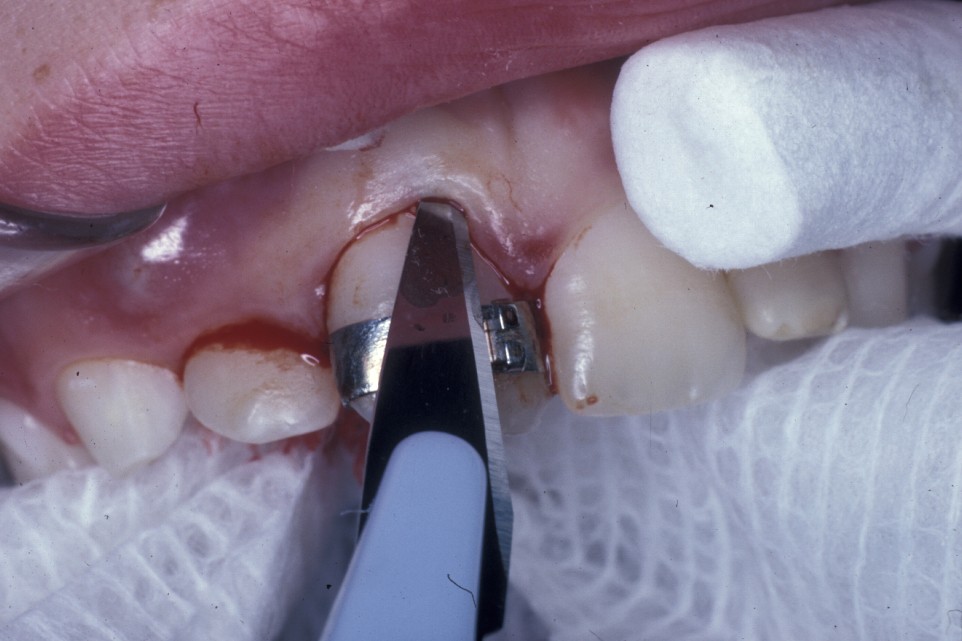

Closed eruption uses an attachment secured to the tooth to apply orthodontic traction and is useful in the treatment of markedly ectopic teeth where it would be difficult to undertake an adequate open exposure. It is often used when the canine is palatally positioned. It can be used for the treatment of buccal canines but the results can be disappointing if the attachment herniates through the thin buccal gingivae. To avoid this, the attachment should be placed either on the tip of the tooth or palatally. This is sometimes not possible because the crown position increases the risk of either excessive bone removal or iatrogenic damage to adjacent structures. It is, however, useful in the treatment of buccal canines if the crown overlies an adjacent tooth and it would be difficult to undertake an apically repositioned flap.

Surgery involves the same access as for the removal of the tooth, except that great care must be taken not to damage the cementum of the root surface as this can lead to ankylosis of the tooth and subsequent failure of eruption. An adequate amount of the crown should be exposed to allow attachment of the bracket and chain. Prior to bonding the bracket to the tooth, the area should be as uncontaminated as possible. Bleeding should be arrested as much as practicable with the use of local application of vasoconstrictors (as is added to some local anaesthetics) or the use of diathermy. Once the area is prepared, the tooth surface should be washed with saline or water and then prepared for bonding either with acid etch or with self-etch priming agents. The latter offer the advantage that they do not need to be rinsed off, need less time to prepare the tooth and are to some extent hydrophilic.

Once the tooth surface has been prepared the bracket can be secured either with chemical- or light-cured composite. The bracket should be tested to ensure that it is securely in place prior to wound closure. The chain or ligature can either exit through the wound margin on the alveolar ridge or through a stab incision elsewhere if it is felt that this would give a better vector of traction to align the tooth. With teeth that are significantly ectopic or are close to the roots of adjacent teeth, it is sometimes useful for the orthodontist to be present at the time of surgery. This allows an assessment of the relationship of the canine to adjacent structures and to plan the vector of traction that will be most appropriate.